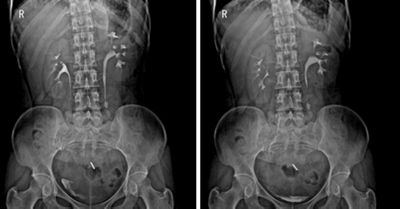

4. 數字化造影:

★將密度和組織器官有差異的造影劑導入人體檢查部位,并檢查組織器官是否存在病變。

★通過動態攝影觀察組織器官的功能運行情況,并輕松進行點片拍攝。

★各種普通及特殊造影,如口服膽囊造影、靜脈膽道造影、T管造影、逆行胰膽管造影(ERCP)、靜脈腎盂造影(IVP)、子宮輸卵管造影、脊髓造影等。